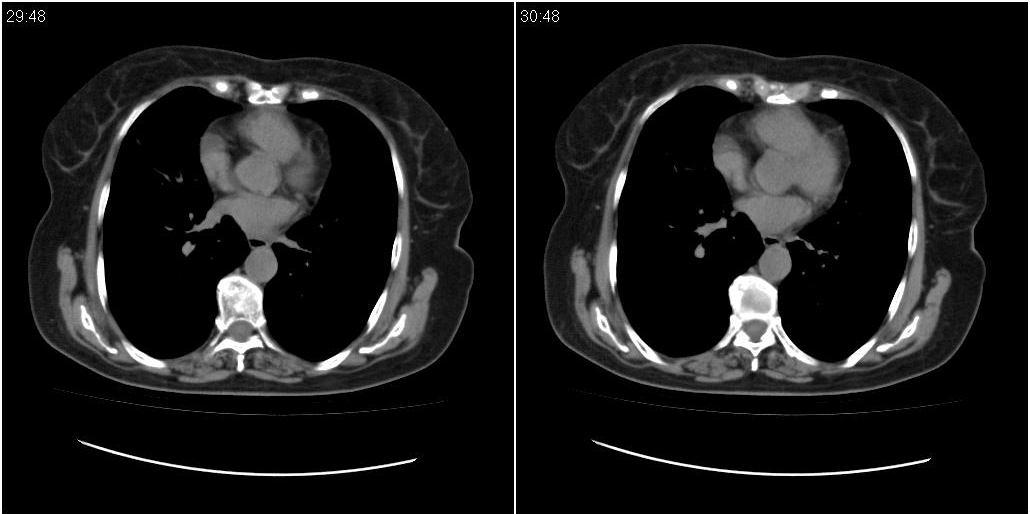

女性,72岁。去年9月份发现肺部病变,诊为肺结核并进行正规治疗至今,但复查后发现ct表现几乎没有变化。

右侧中叶支气管明显狭窄,建议行纤支镜检查!

右中间段支气管局限性狭窄,右中叶支气管亦稍显狭窄,但并未见明显占位表现,半年多了,无变化也许是好事,可能为炎性狭窄,建议继续随访。

双肺继发型tb并右中叶内膜tb,轻度支扩,左下胸膜肥厚粘连。

右中叶炎性改变,支气管狭窄但较光滑,占位可能性不大。

右中间段支气管局限性狭窄,右中叶支气管亦稍显狭窄.

双肺继发性肺结核并右肺中叶节段性肺不张,左下胸膜肥厚粘连。

右肺中叶节段性肺不张,考虑结核或慢性炎症,建议做纤支镜检查。

双肺继发性肺结核并右肺中叶节段性肺不张